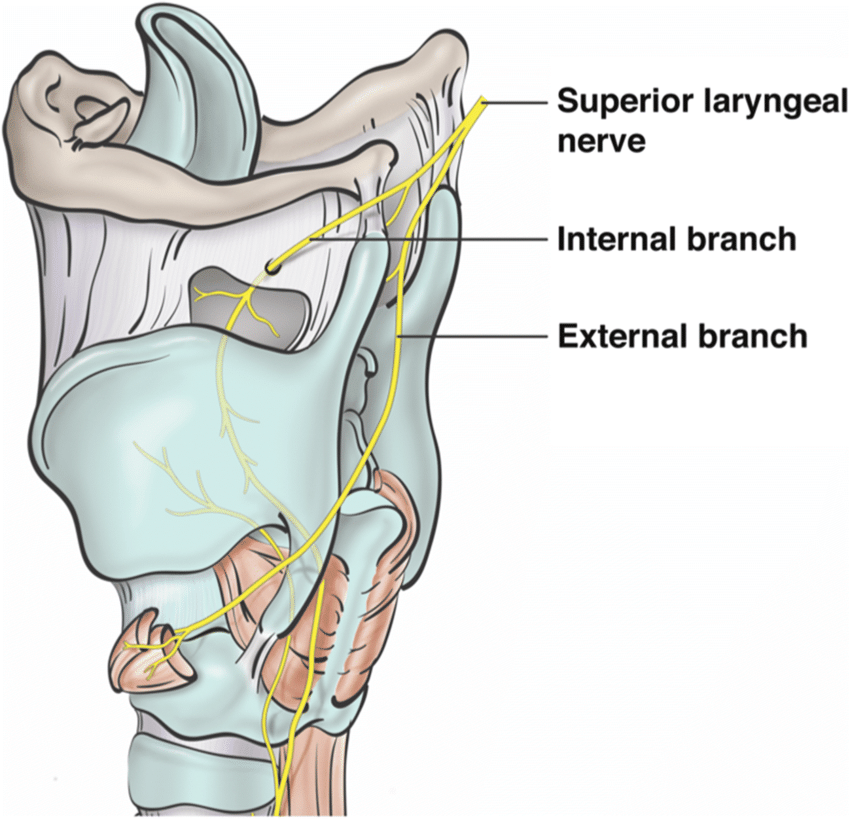

- Sup. laryngeal n.

- Internal br.(Internal laryngeal n.)

- Laryngopharynx

- Larynx (Vocal fold 以上)

- 舌根、Epiglottis 味覺

- External br.

- Cricothyroid m.

- Internal br.(Internal laryngeal n.)

- Sup. laryngeal n.

- Internal br.(Internal laryngeal n.)

- Sensor

- 穿過 Thyrohyoid ligament

- External br.

- Motor

- Internal br.(Internal laryngeal n.)